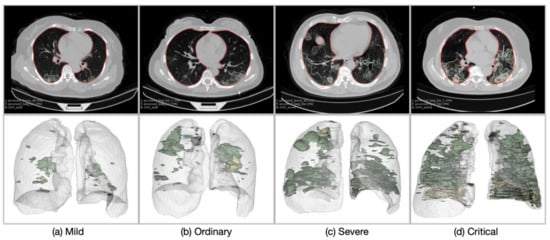

The lung masks generated using the R231CovidWeb model [31] and the lesion masks generated by the lesion encoder module were visually inspected by an experienced image analyst (S.L.). Overall, the lung segmentation results were visually reliable with few severe and critical cases having infection areas missed out in their lung masks. The lesion encoder achieved a Dice of 0.92 on the COVID-19 CT segmentation dataset [32]. Figure 4 presents four examples of the lung and lesion segmentation results (reconstructed using 3D Slicer (v4.6.2) [40]) of the COVID-19 patients, one for each severity class. It shows that higher severity of COVID-19 is reflected in CT scans as increasing number and volume of lesions.

Figure 4. Examples of the patients in different severity groups: (a) Mild, (b) Ordinary, (c) Severe, and (d) Critical. The upper row presents the axial CT slices with the lung (red) and lesion (green: GGO; yellow: consolidation; brown: pleural effusion) boundaries overlaid on the CT slices. The lower row illustrates the 3D models of the lung and lesions.